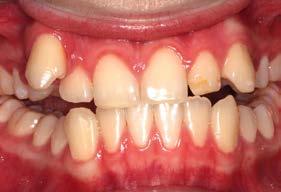

Figura 3. Lateral derecha. Figura 4. Izquierda de inicio. Figura 5. Frente. Figura 6. Overjet, laterales derecha e izquierda.

Las fotografías intraorales muestran las relaciones molares clase II y las relaciones caninas clase II bilaterales (Figura 3 y 4), espaciamiento anterosuperior, un overjet y overbite aumentado (Figura 5). La forma de los arcos es cuadrada, superior e inferior, con el apiñamiento moderado inferior y los espacios en superior.